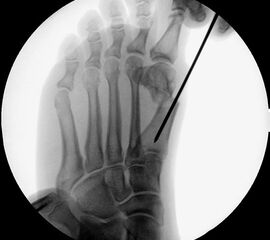

Abbildung 1

• Korrekturpotential größer als beim offenen Chevron, da die Gelenkkapsel als stabilisierendes Element erhalten bleibt und über eine trikortikale Osteosynthese mit zwei kanülierten Schrauben eine Verschiebung bis ca. 80% des Metatarsaledurchmessers möglich ist (Abb. 1).